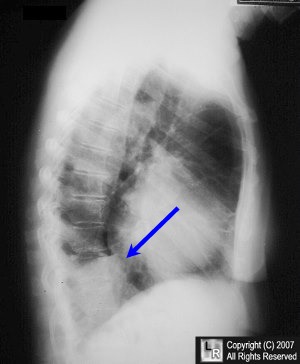

"Spine Sign" Due to LLL Atelectasis

A lateral view of the chest shows an area of increased density (blue arrow) above the left hemidiaphragm which silhouettes the left hemidiaphragm. The atelectatic lower lobe is producing increased density of the lower thoracic spine called the spine sign.